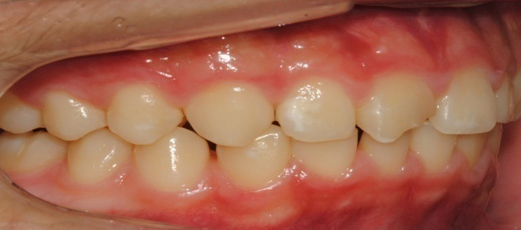

À§ ȯÀÚ´Â À´Ï°¡ ¾Æ·§´Ï¸¦ ³Ê¹« µ¤¾î¿ä(°ú°³±³ÇÕ) ¸¦ ÁÖ¼Ò·Î ³»¿øÇÑ ÃʵîÇлýÀ̾ú½À´Ï´Ù. ÅμºÀå ¾ÇÁ¤ÇüÀåÄ¡ »ç¿ëÈÄ È£ÈíÀÌ °³¼± µÇ¾úÀ¸¸ç Ä¡·áÀü¿¡ ºñÇØ ۰¡ 10cmÁ¤µµ ±Þ¼Ó ¼ºÀåÇÏ¿´½À´Ï´Ù.

°ú°³±³ÇÕ°ú ¹«ÅÎ,ÅΰüÀýÀ» ÁÖ¼Ò·Î ³»¿øÇÏ¿© ÅμºÀå ¾ÇÁ¤ÇüÀåÄ¡¸¦ ÀÌ¿ëÇÏ¿© Ä¡·áÁßÀΠȯÀÚ·Î Ä¡·á½ÃÀÛ½ÃÁ¡ ±âÁØÀ¸·Î ÇöÀç ۰¡ ¾à 8cmÁ¤µµ ¼ºÀåÇÏ¿´½À´Ï´Ù. (Âü°í·Î 2³âÂ÷ ¿©µ¿»ý°ú ۰¡ 7-9cmŰ Â÷À̳²)